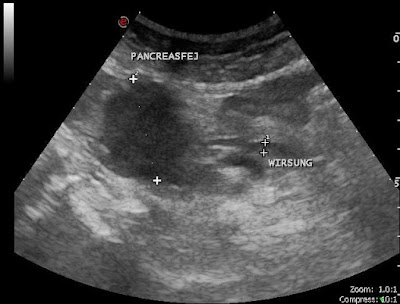

Idős hölgy sárgasággal

- Pancreas